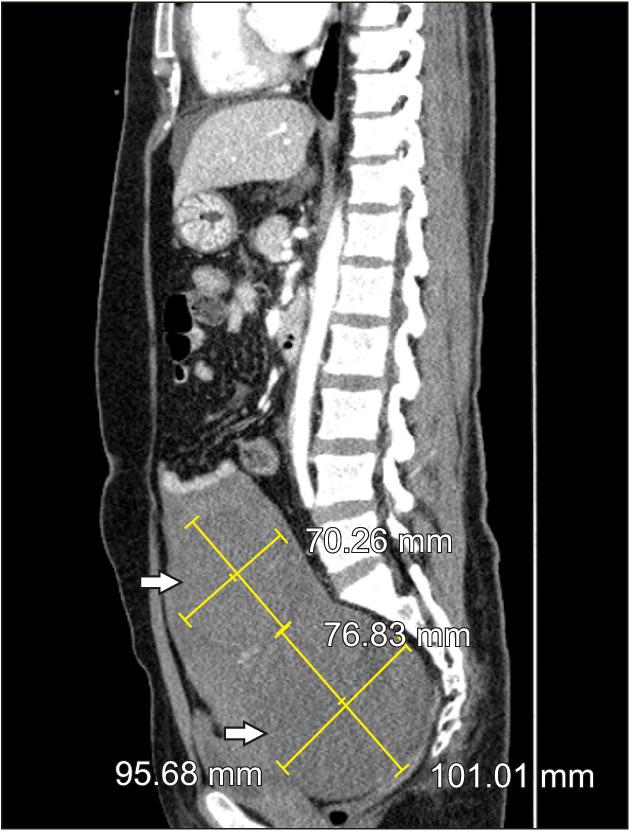

Uterine fibroid, or leiomyoma, is a common benign neoplasm in women, but serious complications are rarely reported. We present the case of a 48-year-old woman with acute onset of abdominal pain. She was hemodynamically unstable, and computed tomography revealed abundant fluid collection in the peritoneal cavity, suggesting hemoperitoneum. During emergency exploratory laparotomy, the subserosal vein overlying a uterine fibroid was identified as the source of bleeding. Hemostasis was accomplished with fibroid excision. Spontaneous hemorrhage originating from a uterine fibroid is extremely rare, but may lead to life-threatening conditions. Therefore, in female patients with acute abdominal pain and hemoperitoneum, uterine fibroid may be a potential etiology and emergency exploratory laparotomy should be considered.

摘要

子宫肌瘤,又称平滑肌瘤,是女性常见的良性肿瘤,但严重并发症鲜有报道。我们报告一例48岁急性腹痛女性病例。她血流动力学不稳定,计算机断层扫描显示腹腔内有大量积液,提示腹腔积血。在急诊剖腹探查术中,发现子宫肌瘤表面的浆膜下静脉是出血来源。通过切除肌瘤实现了止血。子宫肌瘤自发出血极为罕见,但可能导致危及生命的情况。因此,对于急性腹痛和腹腔积血的女性患者,子宫肌瘤可能是潜在病因,应考虑急诊剖腹探查术。